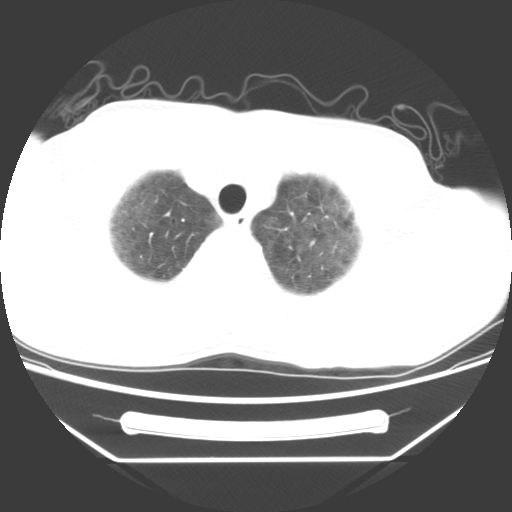

病人55岁,咳嗽,胸闷

忘了传病史了,病人55岁,咳嗽,胸闷

两肺部呈“毛玻璃”状改变,原因待查考虑感染性病变

病人是否发烧,两肺“磨玻璃”影,其间见空气支气管征和碎路石征。考虑肺泡蛋白沉着症。

两肺广泛对称磨玻璃样影,密度不均,考虑机遇性肺部感染。

双肺弥漫磨玻璃样病变,病史很重要。有感冒或发烧史,甲流不除外。无发烧可考虑肺泡蛋白沉积,但肺泡蛋白沉积边缘往往较清晰,与正常肺组织分界清晰

两肺弥漫间质性病变,考虑肺泡蛋白沉着症。建议进一步检查。